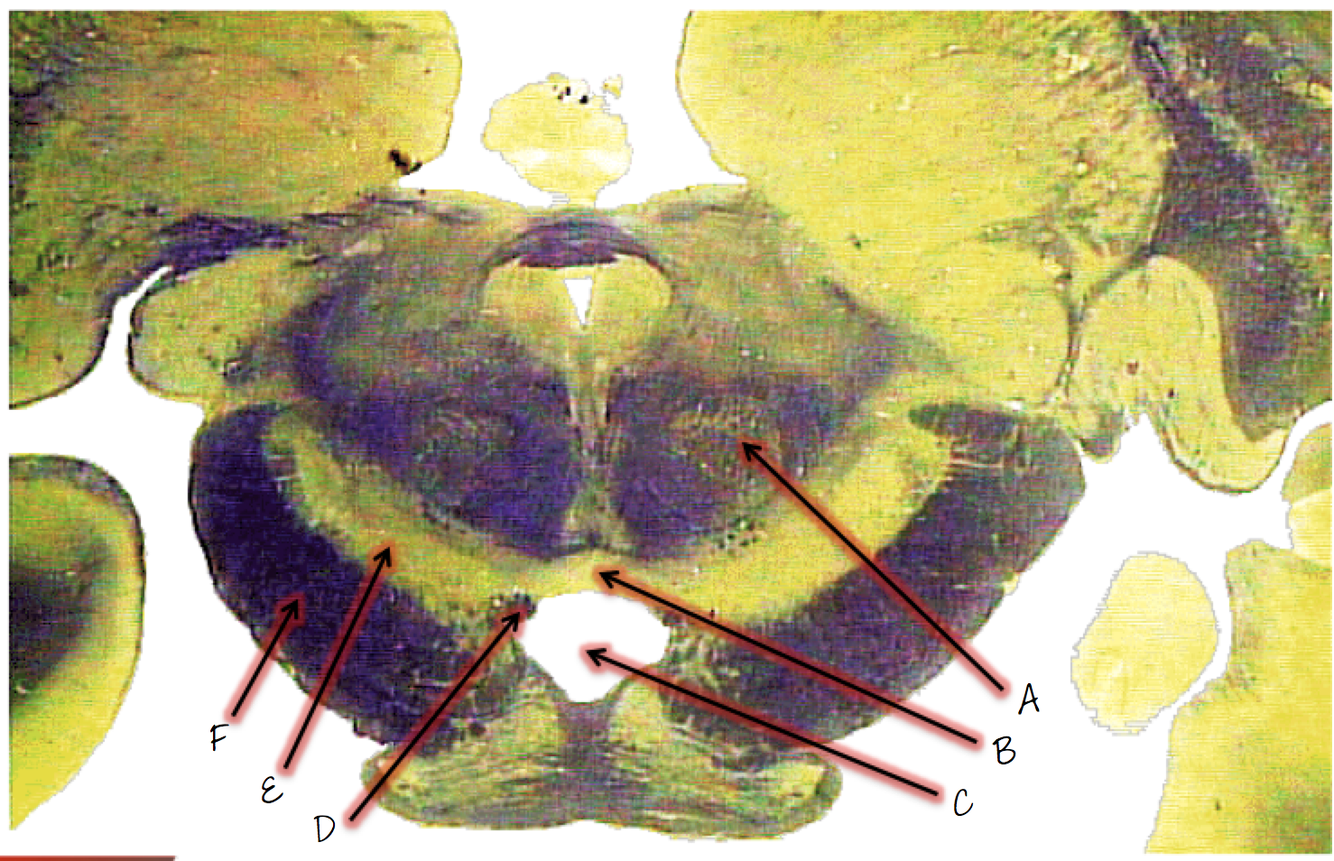

A; red nucleus

B; ventral tegmental area

C; interpeduncular fossa

D; fibers of the oculomotor nerve (CNIII)

E; substantia nigra

F; crus cerebri (crebral peduncle)